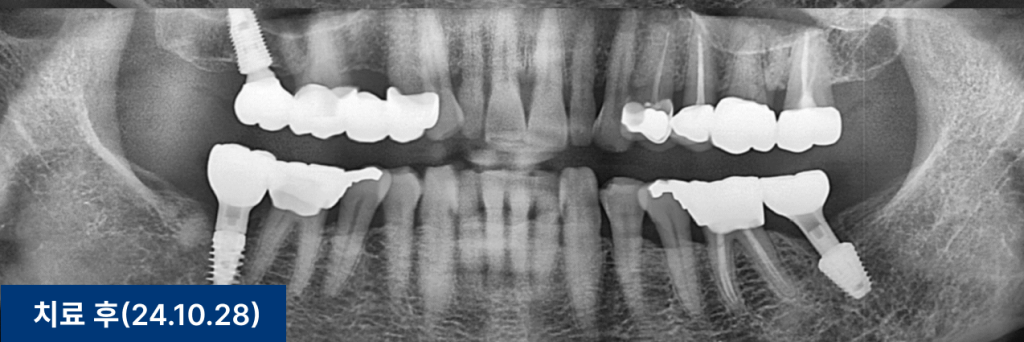

최종 보철물은 귀국 시기에 맞춰 맞춤 제작하여 완성했습니다.

환자분은 과거에 시술받은 임플란트 중

일부 보철물이 파절된 상태였습니다.

하지만 다행히 임플란트 본체는 건강하게 유지되고 있었습니다.

이에 따라 기존 임플란트는 그대로 두고,

상부 보철물만 새로 제작했습니다.

이번에는 교합면 방향과 잇몸 형태를 고려하여

맞춤형 지대주(abutment)를 적용했습니다.

이는 향후 파절 위험을 줄이고

심미적 완성도를 높이는 데 도움이 됩니다.